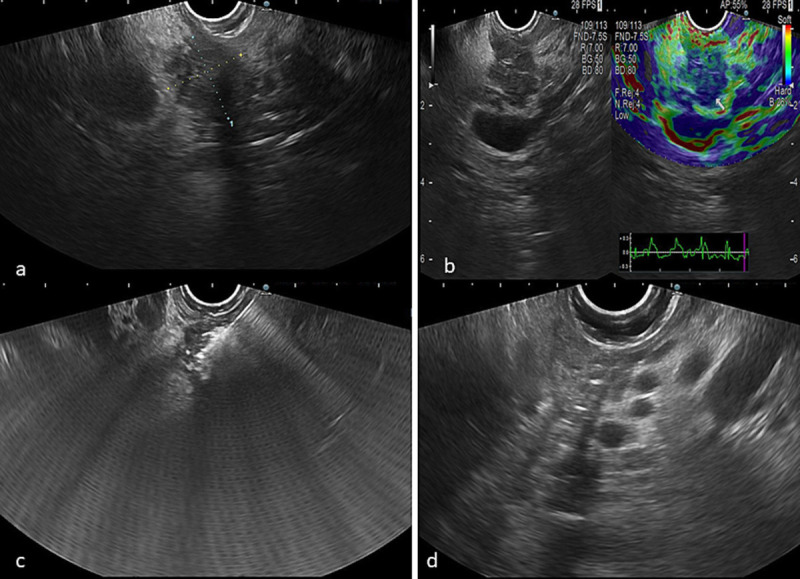

A novel case of EUS-guided targeted radiofrequency ablation of metastatic duodenal renal cell carcinoma.

eus引导下靶向射频消融术治疗转移性十二指肠肾细胞癌一例。